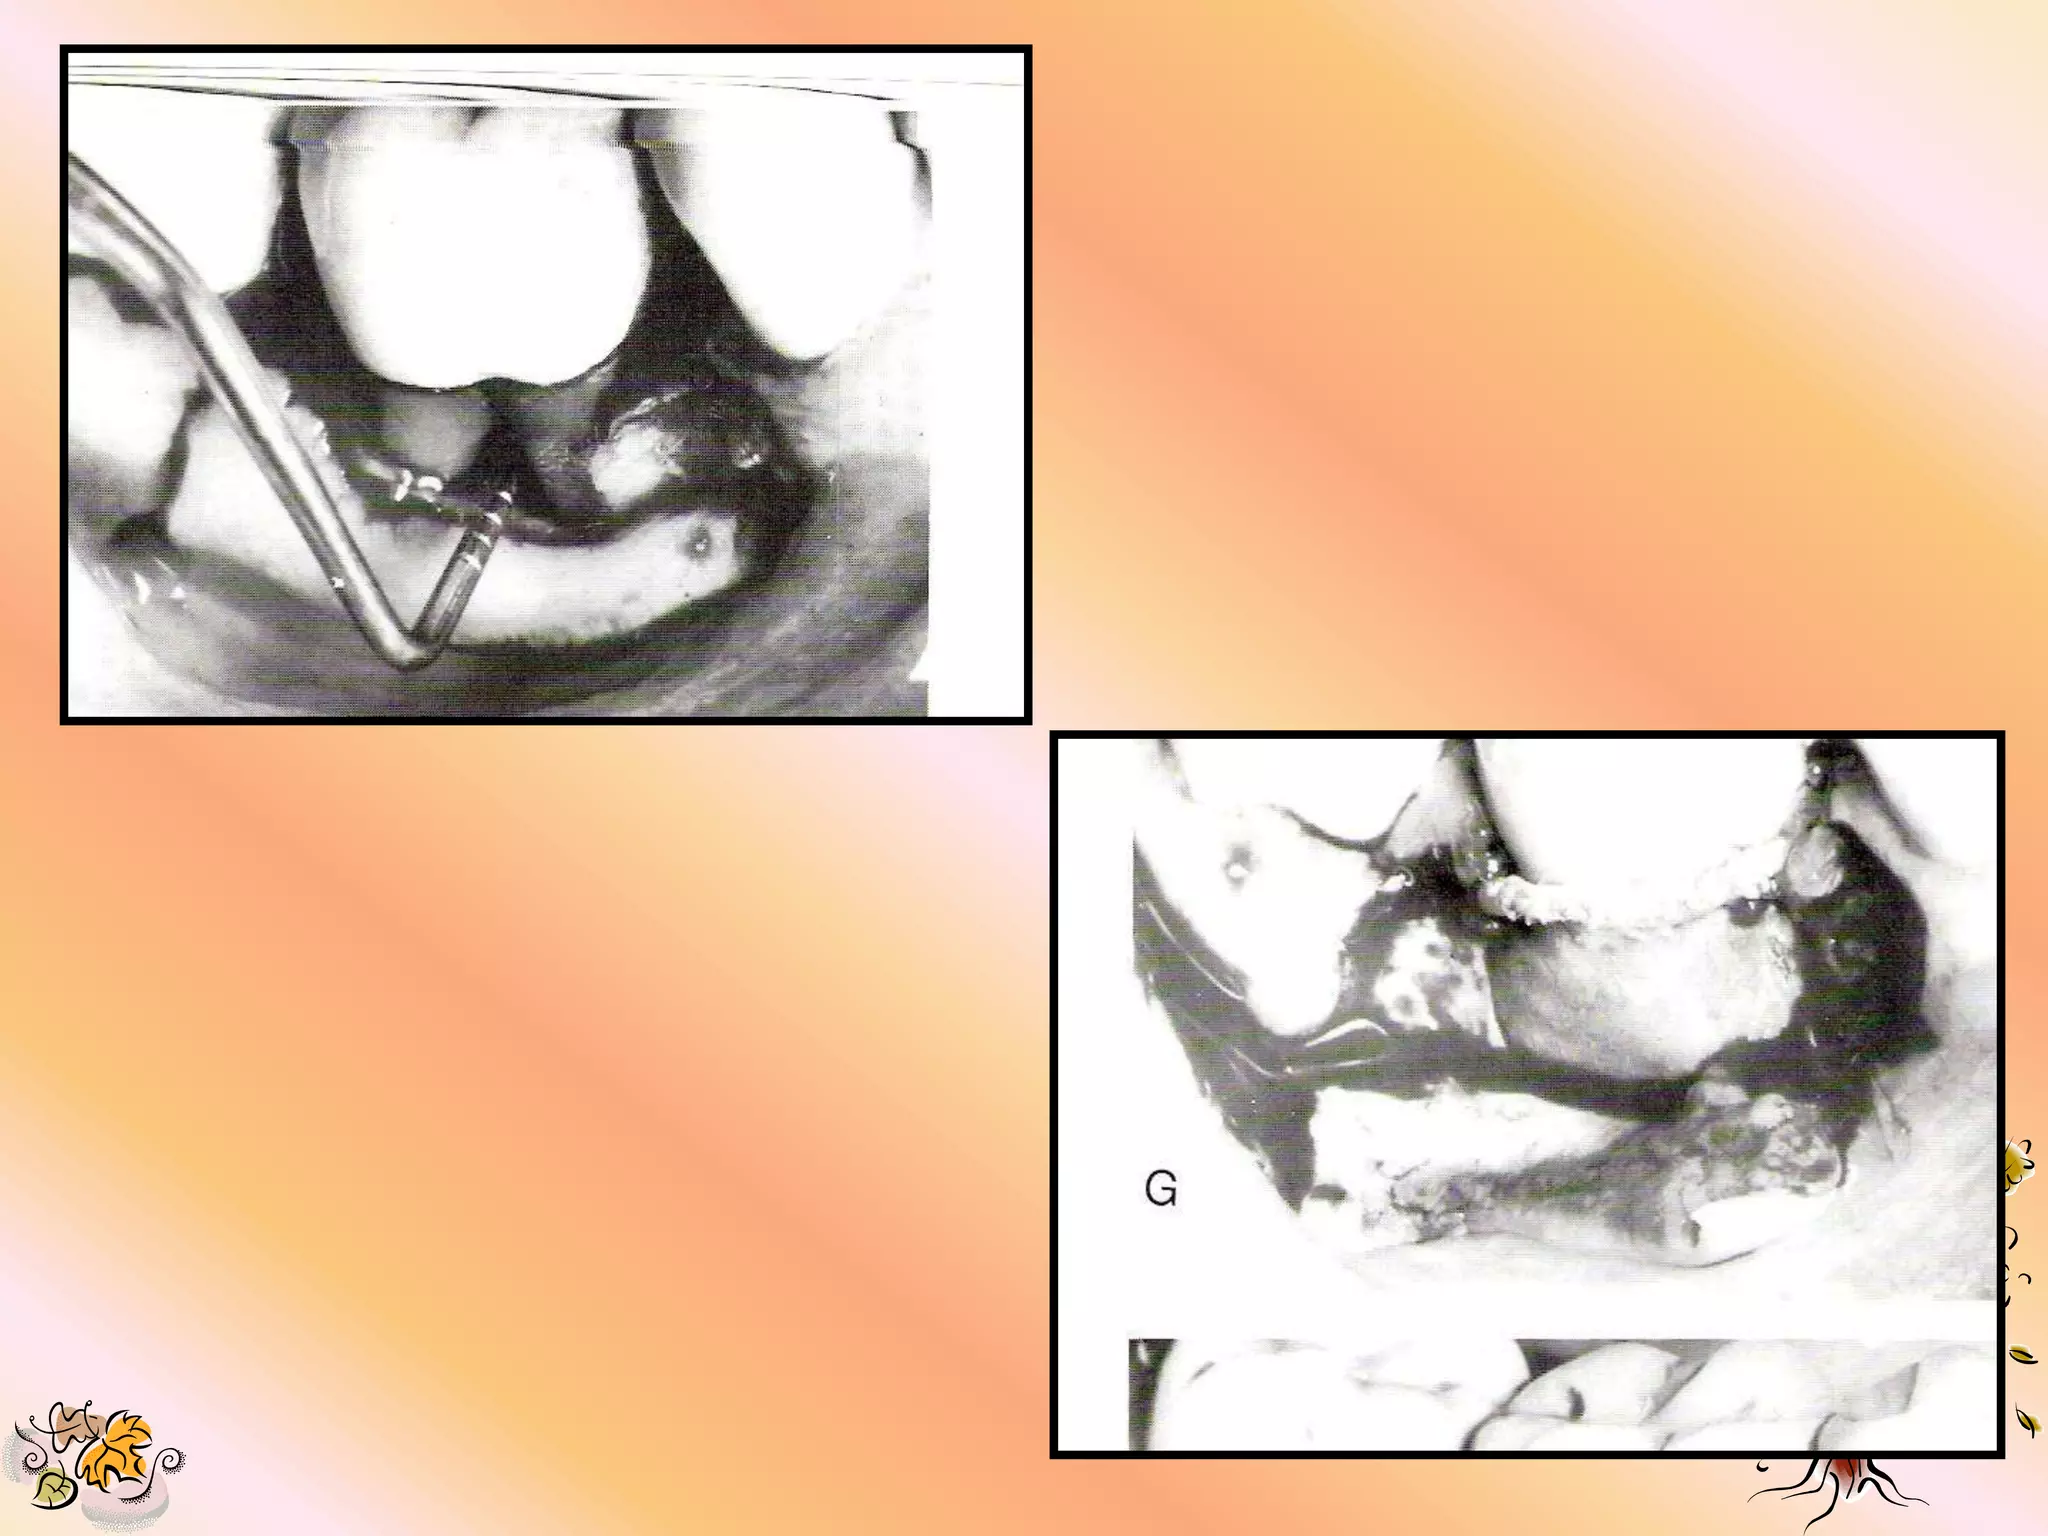

PRIMARY INCISIONS 1. Intra sulcular incisions are made in preparation for a full mucoperiosteal flap. 2. All residual pocket epithelium is removed after flap reflection to permit integration b/w the e-PTFE & flap connective tissue. 3. Incision should extend 1-2 teeth mesial &/ or distal of the area being treated to permit adequate visualization. 4. Vertical incision should be placed mesially where necessary.

DEFECT PREPARATION 1. Degranulationof defect. 2. Scaling & root planning for removal of all tooth deposits. 3. Decortification of bone for increased vascularity & scratching of the PDL to stimulate cell & vascular proliferation.

SELECTION & PLACEMENTOF GORE-TEX PERIODONTAL MATERIAL 1. Maintain sterility of material. 2. Choose a size that offers the most ideal design for defect coverage. 3. Shape the material with scissors, avoid leaving sharp edges.

4. Enough materialshould be left to permit lateral & interproximal suturing while leaving at least 3 mm apical & lateral overextension of defect margins. 5. Do not remove the open microstructure or coronal portion of the material. It can be trimmed on the lateral aspect. 6. The material should fit smoothly, avoiding folds, overlaps & protrusions which may compromise the overlying gingival tissue.